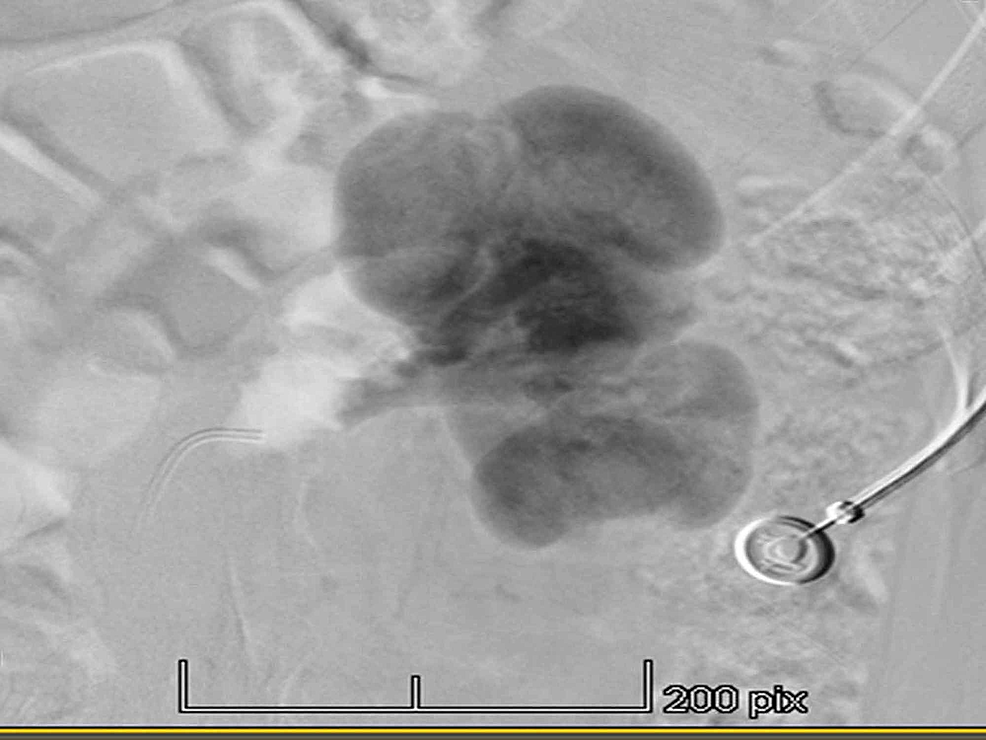

Figure 1 from Can Nutcracker Syndrome cause secondary hypertension? Two

Figure 1 from Can Nutcracker Syndrome cause secondary hypertension? Two Nutcracker Syndrome And Hypertension nutcracker syndrome is the compression of your left renal (kidney) vein, usually between your abdominal aorta and superior. the orthostatic proteinuria noted in some patients with nutcracker syndrome may be caused by positionally or posturally induced. nutcracker syndrome (ncs) describes left renal vein compression between the superior mesenteric artery and the aorta. nutcracker syndrome (ncs) is. Nutcracker Syndrome And Hypertension.